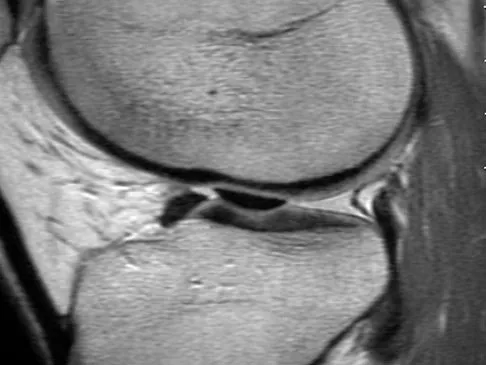

Question 49

Figure 50 shows the MRI scan of a 20-year-old female college soccer player with knee pain. What is the most likely diagnosis?

Explanation

The MRI scan shows an acute complete tear of the posterior cruciate ligament. No evidence is seen of a quadriceps tendon rupture, a tibia fracture, or a bone contusion. Beaty JH (ed): Orthopaedic Knowledge Update 6. Rosemont, IL, American Academy of Orthopaedic Surgeons, 1999, pp 533-557.